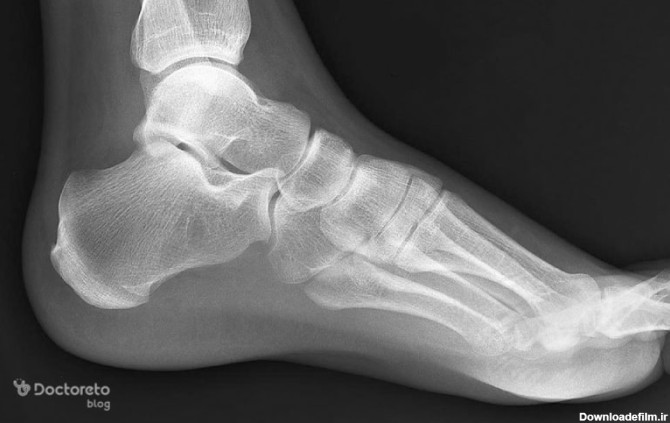

رادیولوژی مچ و کف پا در منزل تهران و کرج رادیولوژی در منزل مچ پا و کف پای انسان یک روش تصویربرداری پزشکی است که برای مشاهده و تحلیل ساختارهای داخلی مچ پا، از جمله استخوانها، مفاصل، و بافتهای نرم، به کار میرود. عکس مچ پای انسان به ویژه در تصویربرداری مچ پا، میتواند در تشخیص شکستگیها، آسیبها، التهابات، یا مشکلات مربوط به استخوانها و مفاصل کمک کند. رادیولوژی در منزل مچ پا و مچ دست در منزل تهران و کرج یک روش تصویربرداری پزشکی است که برای مشاهده و تحلیل ساختارهای داخلی مچ پا، از جمله استخوانها، مفاصل، و بافتهای نرم، به کار میرود. عکس مچ پای انسان به ویژه در تصویربرداری مچ پا، میتواند در تشخیص شکستگیها، آسیبها، التهابات، یا مشکلات مربوط به استخوانها و مفاصل کمک کند.

برای درمان شکستگی مچ پا ابتدا باید تشخیص به درستی صورت بگیرد. مهم ترین ابزار برای تشخیص این نوع شکستگی بررسی تصاویر رادیوگرافی است.